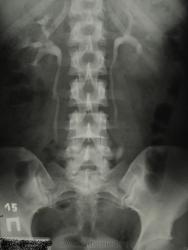

В наблюдении, похоже, имеются аберрантные внутрипочечные сосуды обеих почек; каликоэктазия (не врождённая же), больше справа, что служит основанием для дообследования больной (включая доплерографию сосудов почек...) Не факт, что гломерулонефрит единственный/правильный диагноз!..

3.Цель исследования при гломерулонефрите??? Хорошо, допустим у неё есть в почке(одной, как видно по этим снимкам) аберрантный сосуд. И что? Прожила она с ним 18 лет и ничего, а утверждать, что он(сосуд) как-то повлиял на возникновение гломерулонефрита - шаманизм.

4.Размеры ЧЛС нормальные.

3 и 4 - Гломерулонефрит - страдание паренхимы, каликоэктазия (убеждён, имеет место) "цветёт" не на пустом месте, при длительной задержке мочи в ЧЛС - страдает паренхима. Надеюсь, ход мысли понятен. А сосуды (и аберрантные) с возрастом изменяются - уплотнённые, ригидные нарушают отток мочи в большей степени...